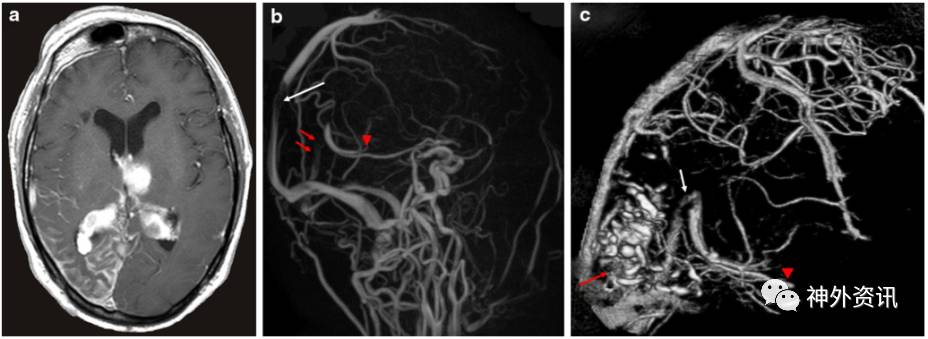

62岁患者男性,因突然昏迷入院,GCS评分6分,伴右侧轻偏瘫。在患者右侧面部三叉神经第1支分布区可见葡萄酒色血管痣,符合斯特奇-韦伯综合征皮肤表现。患者既往右眼视力下降,无青光眼、无癫痫和卒中发作病史。实验室检查提示患者有脱水表现,红细胞压积升高和D-二聚体上升。CT扫描显示左侧丘脑出血破入脑室伴急性脑积水,双侧脉络丛增大;右侧枕颞叶皮质下片状钙化(图1)。给予患者施行急诊脑室外引流术,术后7天GCS评分恢复至15分,右侧轻偏瘫逐渐好转。MRI扫描显示左侧丘脑出血、右侧颞枕叶软脑膜增强、双侧脉络丛增厚;MRA示直窦、左大脑内静脉和上矢状窦急性闭塞。予以补液和抗血栓形成治疗。2周后三维CT扫描提示直窦、左大脑内静脉和上矢状窦开放(图2)。术后3周,患者GCS评分15分,右侧轻偏瘫进一步好转,开始在辅助下行走。

图2. a.MRI增强扫描显示左侧丘脑出血、右侧颞枕叶软脑膜强化、双侧脉络丛增厚;b.MRA示直窦(红色箭头)、左大脑内静脉(红色三角)和上矢状窦(白色箭头)急性闭塞;c.治疗后2周,三维CT扫描提示直窦(白色箭头)、左大脑内静脉(红色三角)和上矢状窦开放,右侧枕叶皮质下钙化(红色箭头)。